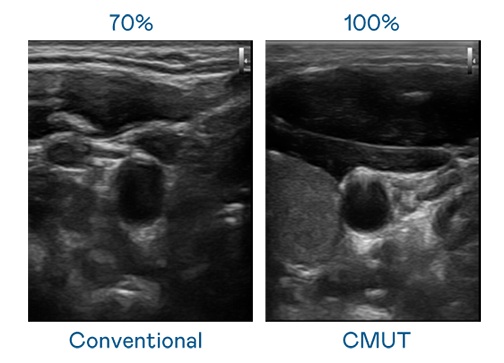

CMUT 技术是一种用电容式微机电元件来产生超音波讯号的技术。与传统 PZT 压电式技术相比,CMUT 频宽增加 30%,更宽频的超音波讯号让影像解析度大幅提升,是实现高影像品质医疗超音波扫描、促进精准医疗发展的关键技术。

大频宽带来超清晰影像

超音波影像的解析度高低,首先取决于探头能发出的讯号频宽。NG28 CMUT 可提供高清晰的超音波讯号,提供高频宽、高灵敏度、影像纹理细节更高的超音波影像,协助医护人员缩短影像判读时间及利用精准的医疗影像进行诊断。